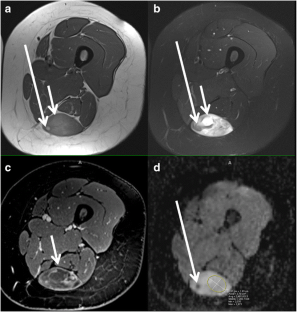

Fig. 3